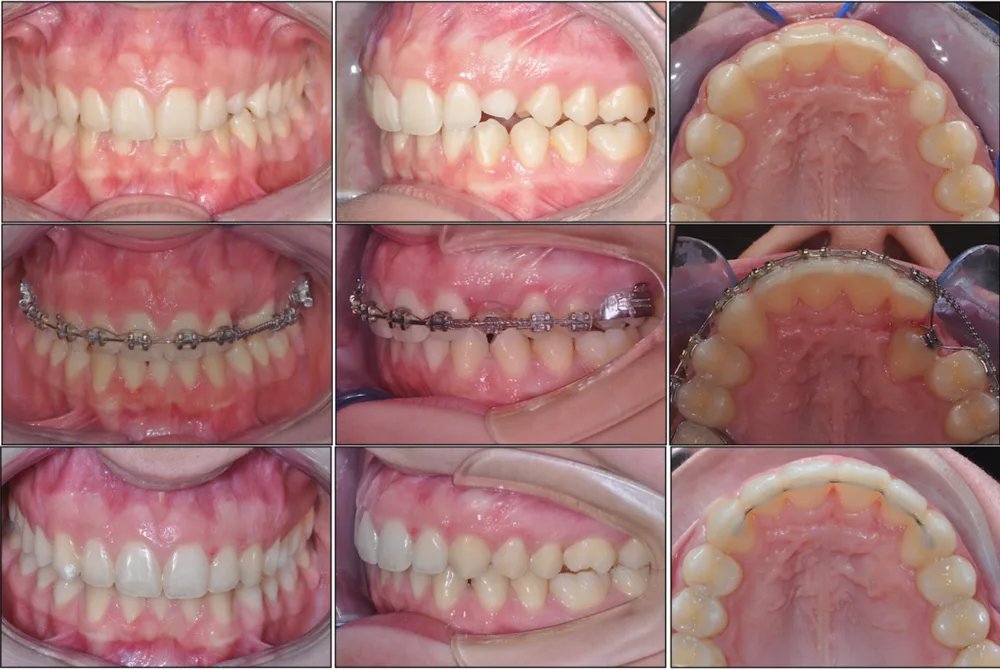

Spesso sono necessari apparecchi ortodontici per poter aiutare questi denti a ritrovare la loro strada. In alcuni casi è necessaria anche una piccola collaborazione chirurgica per esporre il dente e applicarvi un attacco ortodontico.

Una volta esposto chirurgicamente il dente incluso, si applica un attacco ortodontico che permette di guidarlo gradualmente verso la sua posizione corretta nell'arcata.

Il trattamento richiede un lavoro di squadra tra l'ortodontista e il chirurgo orale, con tempistiche pianificate con cura per ottimizzare il risultato.